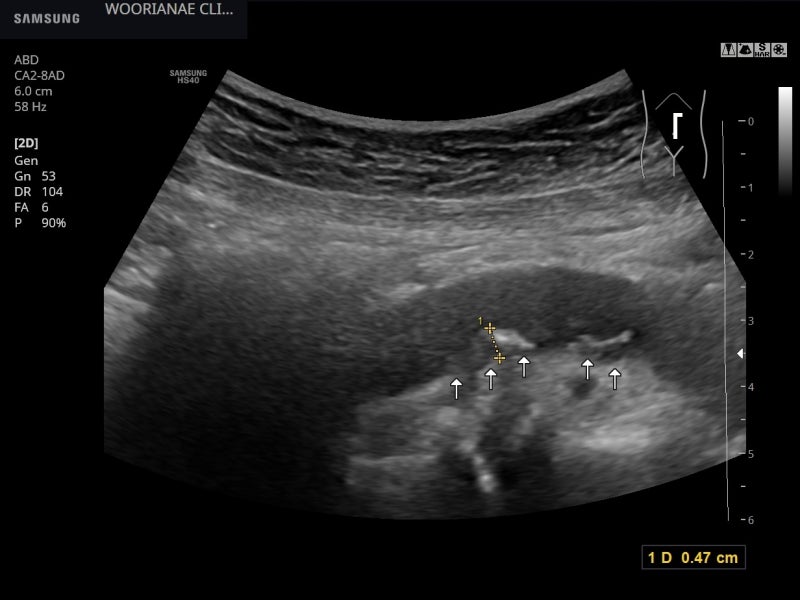

대동맥의 비틀림 등을 제거하기 위해 혈관도 관찰하는데… 명확한 동맥경화, 플라크(plaques)가 관찰된다; 20대부터 흡연력

비틀림형 확장 소견(aneurys malchange)은 없었으며 동맥 주변에 저음영 이상 소견은 관찰되지 않았다.

플라크를 타고 흐르는 혈류의 모습